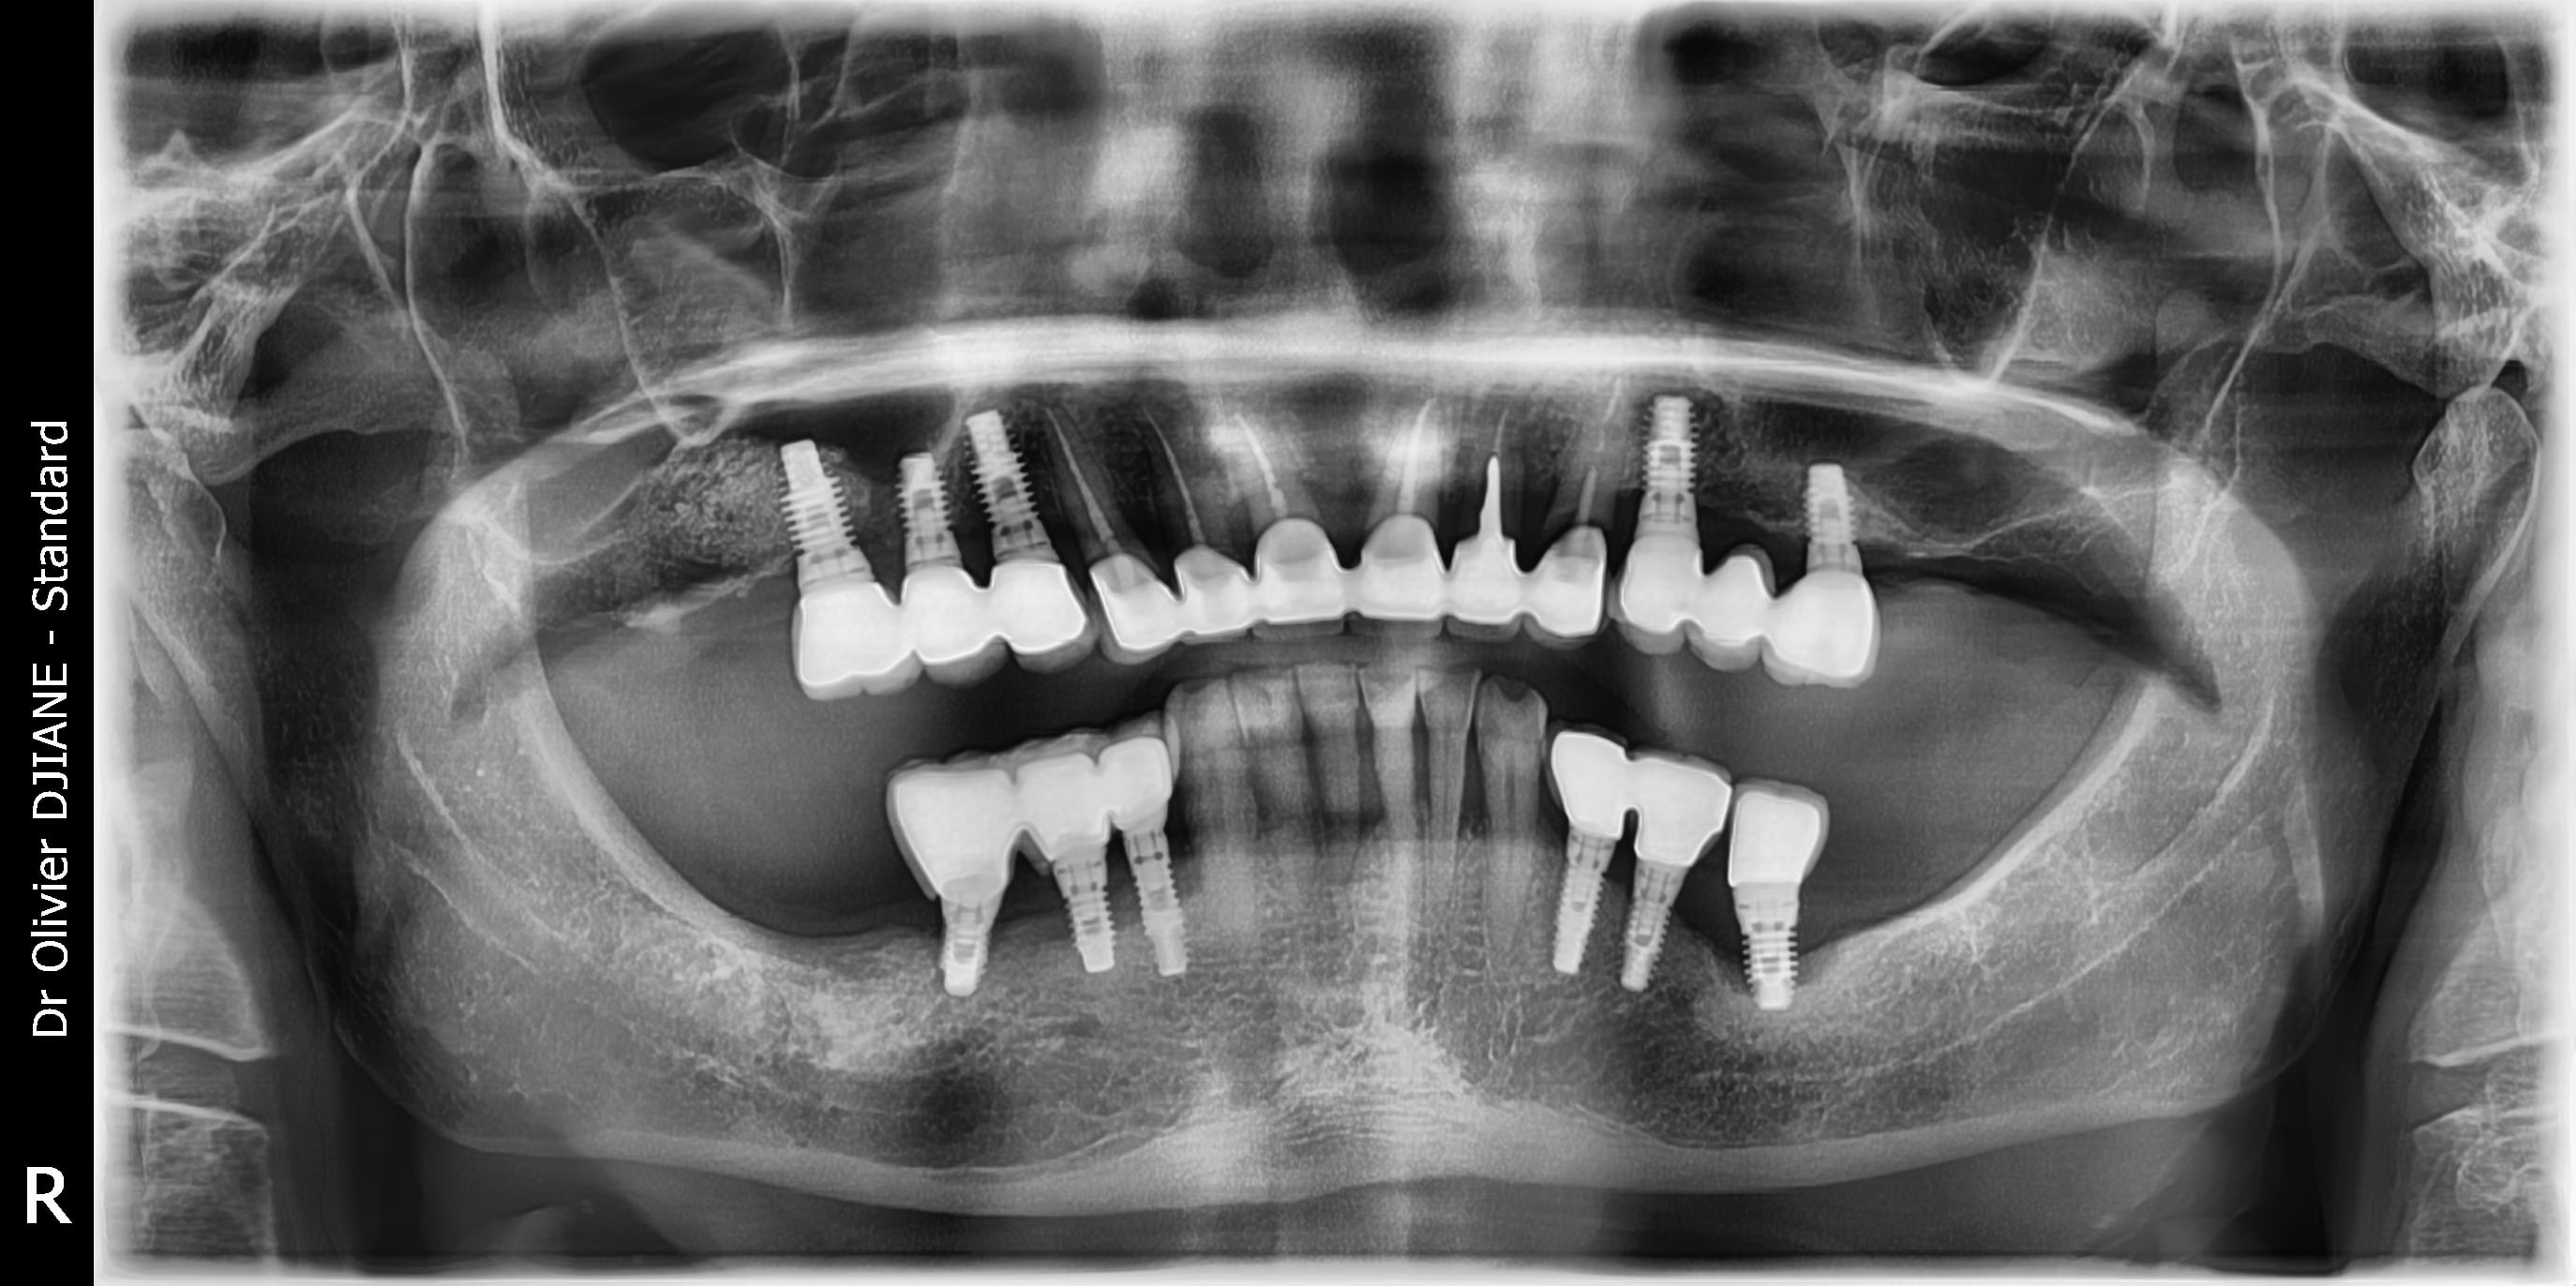

je vais entamer ma première MCEI de 13 à 23 .

J'ai choisi comme schéma la pose en 13 12 22 23 , en 11 et 21 la présence du paquet vasculonerveux palatin antérieur me refroidit.

Faut vraiment enlever ces 6 dents ?

les retros .... d apres toi je lui mets 2 implants en 13 et 23 et on attends 4 ans que 12 22 bougent ?

A 4 ans, je suis plus inquiet pour le bas que pour 12 et 22.

22 et 23 ont clairement des pêches, c’est une contrindication pour une implantation immédiate, alors pour une mci, encore plus.

Je n’ai pas tout le scan, mais en 11 et 21, je ne vois pas vraiment le problème. Je ne comble pas mes extractions, je ne vois pas l’interêt.

Mettre en sous occ, une mci c’est une très bonne idée, mais dans ton cas, ça veut dire que les seuls contacts resteront sur 45-46 et 35-36. 3 d’entre elles sont déjà perdues, que ce passera-t-il en 6 mois?

Enfin, on a pas tout le dossier, mais c’est vrai que je ne pense être parti directement sur ce plan de traitement. Peut-être plutôt, nouvelle couronne sur 23 ou extraction puis implant en temporisant avec une couronne en extension sur 22. En même temps, résection apicale pour 22 et les autres s’il faut. Et surtout , reprendre les deux secteurs postérieurs mandibulaires. ( extraction de 18, aussi, ça fait négligé sur la pano...).

Dans ton plan de traitement, à cause des infections et des secteurs postérieurs , tu ne peux pas faire de mci, ce sera donc de long mois avec une ppa inconfortable pour le patient et pas bon pour la cicatrisation d’un point de vue esthétique.